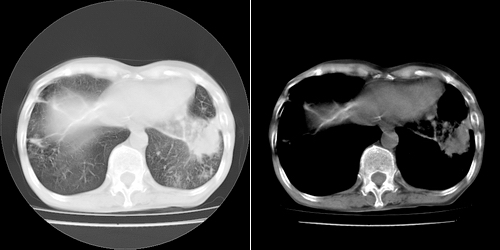

以下是引用lihuuuu在2006-7-18 18:16:00的发言:[br]支持肺结核诊断[br]本病例符合结核“三多”“三少”特征(多病灶、多形态、多钙化、少肿块、少堆积、少增强)中的前五个特征,另外左下叶背段有不张样改变-考虑伴有支气管内膜结核所致段不张。

以下是引用yang4132在2006-7-18 10:04:00的发言:[br]两肺多发 多形态病变,部分半纤维条索和斑点壮钙化,胸膜肥厚粘连,考虑结核。